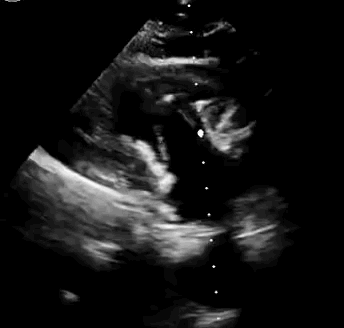

2021年11月14日星期日,復(fù)旦大學(xué)附屬中山醫(yī)院(以下簡稱中山醫(yī)院)葛均波院士團隊成功應(yīng)用經(jīng)血管介入三尖瓣置換產(chǎn)品Lux-Valve Plus完成臨床前研究,并獲得圓滿成功!此次研究的成功預(yù)示經(jīng)血管三尖瓣產(chǎn)品Lux-Valve Plus已完成臨床前準備,即將開啟后期的正式臨床研究!

上海中山醫(yī)院葛均波院士、錢菊英院長、周達新教授、潘文志教授、潘翠珍教授、李偉教授共同完成此次臨床前研究。術(shù)后葛均波院士對Lux-Valve Plus的器械操作性能給予了高度評價,DSA和超聲影像也顯示出在本次研究中Lux-Valve Plus的安全性和有效性俱佳。

本次臨床前研究經(jīng)右側(cè)頸靜脈置入LuX-Valve Plus輸送系統(tǒng)可調(diào)彎鞘管,在DSA及超聲引導(dǎo)下將人工三尖瓣瓣膜植入到原有三尖瓣位置,利用獨特的錨定技術(shù)將人工瓣膜支架可靠固定在預(yù)定的位置。

Lux-Valve是全球第一款具有我國完全自主知識產(chǎn)權(quán)的經(jīng)導(dǎo)管介入三尖瓣置換系統(tǒng),利用前瓣夾持及室間隔錨定的復(fù)合方式進行瓣膜裝置的固定,不依賴瓣環(huán)徑向支撐力,同時采用自適應(yīng)復(fù)合裙邊材料,有效的貼合密封柔軟的三尖瓣瓣環(huán),針對于三尖瓣返流的患者有優(yōu)異的療效。Lux-Valve Plus采用全新的經(jīng)血管輸送系統(tǒng),經(jīng)頸靜脈入路創(chuàng)傷更小,可以進一步降低手術(shù)風(fēng)險。相信在后期正式臨床研究開展中,Lux-Valve Plus必定會為更多的三尖瓣反流患者帶來福音。